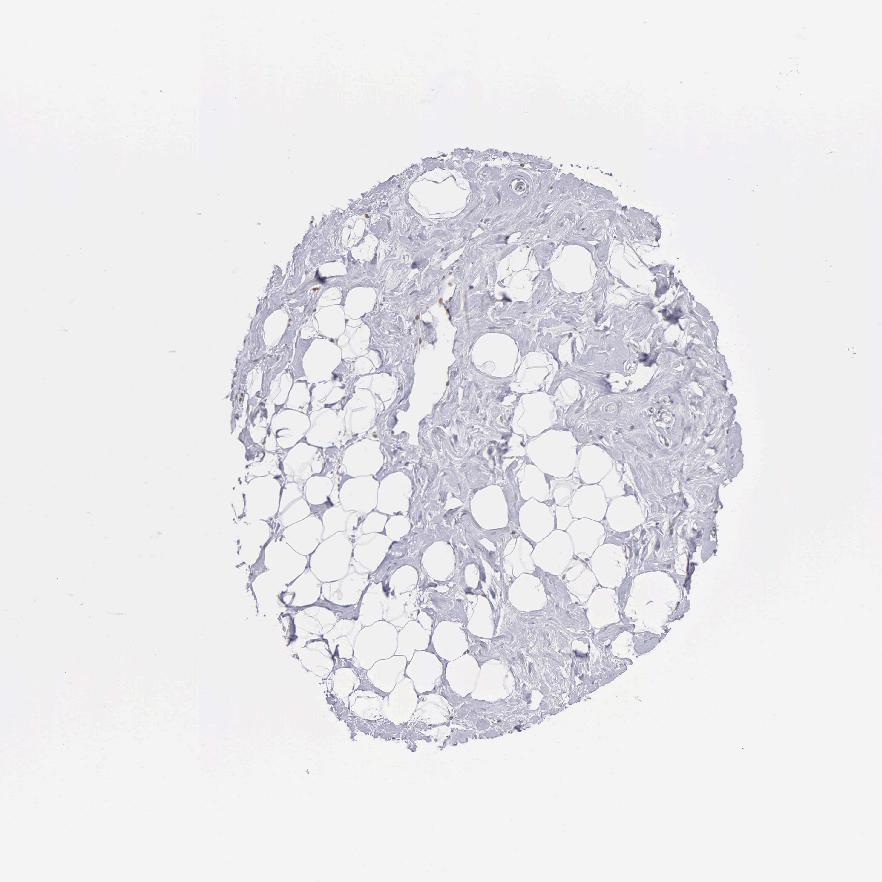

SOFT TISSUE 2 - Antibody stainingi

Antibody staining in the annotated cell types in the current human tissue is reported as not detected, low, medium, or high, based on conventional immunohistochemistry profiling in selected tissues. This score is based on the combination of the staining intensity and fraction of stained cells.

Each image is clickable and will lead to virtual microscopy that enables deeper exploration of all samples and also displays staining intensity scores, fraction scores and subcellular localization as well as patient and tissue information for each sample.

Antibody HPA000807Antibody HPA001063

Fibroblasts Not detectedNot detected

Peripheral nerve -Not detected